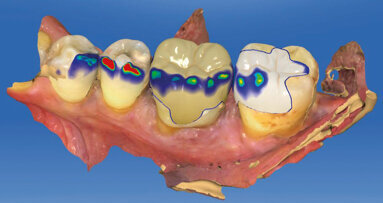

3. Týmová diskuse finálního chirurgického a protetického terapeutického plánu pro hybridní rekonstrukce prostřednictvím kónických bone-level (BLT) implantátů Straumann® s obnovením okluze v rozsahu prvních molárů. Pro výrobu náhrad v podobě kovem vyztužených provizorií v jeden den bylo navrženo využití nepřímé techniky.

4. Koordinace chirurgické návštěvy (dr. Robert Levine) s ordinací protetického lékaře (dr. Harry Randel), zubní laboratoří (NewTech Dental Laboratory, Lensdale, PA) a se zástupcem dentální implantologické společnosti (Straumann USA, Andover, MA). Pacientka si je vědoma možné potřeby nošení jedné nebo obou náhrad během fáze hojení, pokud hodnoty primární stability implantát při inzerci nebudou adekvátní pro imediátní zatížení. To může být způsobeno kvalitou nebo kvantitou kosti nebo potřebou augmentace kosti a membrány pro řízenou kostní regeneraci (GBR) a dvoufázový postup. Toto je velmi důležité prokonzultovat se všemi pacienty, obzvláště pokud jsou plánovány pouze čtyři implantáty v maxile a distální implantát(y) může (mohou) při inzerování vykazovat nedostatečné hodnoty primární stability kvůli kvalitě či kvantitě kosti. Signifikantně zredukovat tuto eventualitu napomáhá schopnost využívat delších, kónických (BTL) a vychýlených implantátů – jako v tomto prezentovaném případu – s adekvátním množstvím bukální kosti použitelným pro plánované implantáty o průměru 4,1 mm.